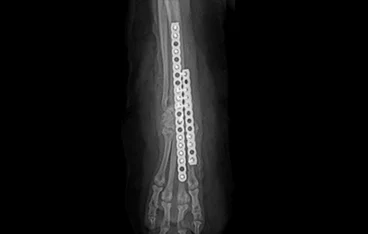

골절

골절 수복(screw, plate, k-wire, pin 등)

• PLATE

• PLATE 수술 전

PLATE 수술 후